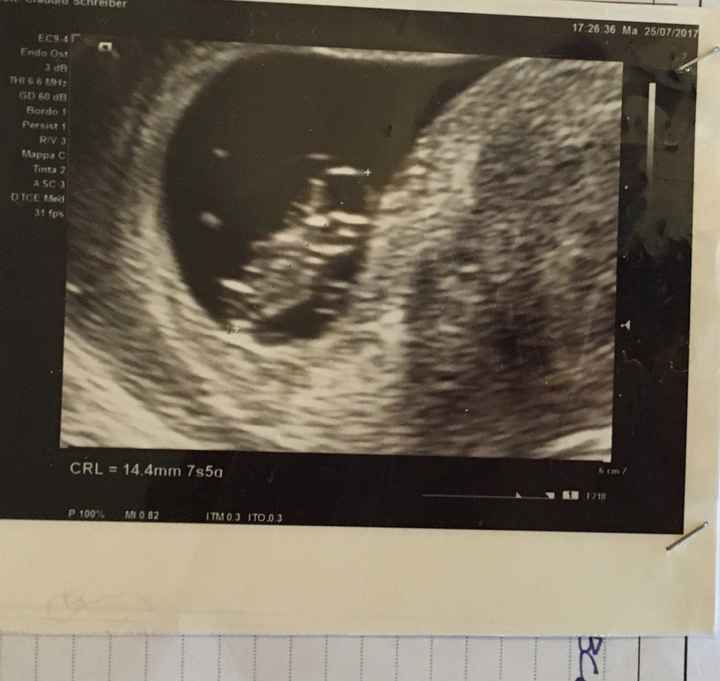

Pubblicato in Future mamme 48